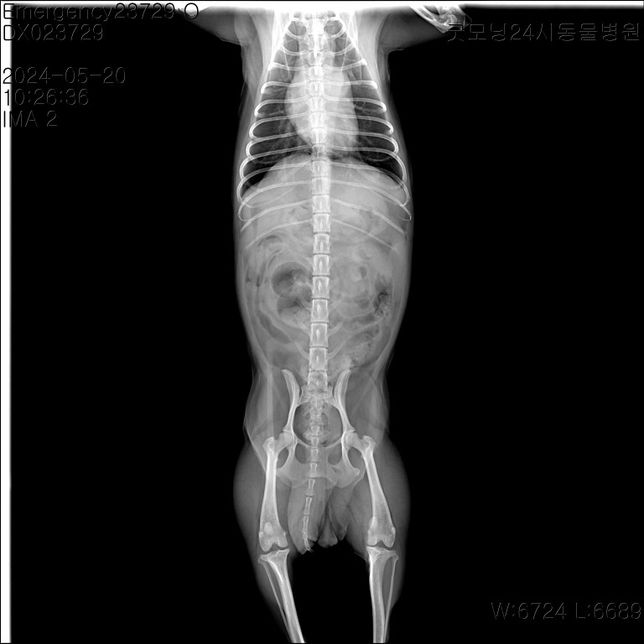

- 반려동물 건강반려동물Q. 강아지 엑스레이 한 번만 더 봐주세요 부탁드립니다어제 유선종양 한 토이푸들 견주입니다. 어제 수술 전 찍은 엑스레이인데 혹시 저 동그라미 친 곳이 유선종양일까요? 종양이 아니라면 뭘까요..? 그리고 엑스레이 상으로 전이소견은 안 보이는 거 맞죠..? 따로 또 문제 되보이는게 있을까요?그리고 종양이 여러개인데 한 개만 조직검사를 의뢰했어요 양성의 결과가 나와도 여러개의 종양 중 한 개만 조직검사를 의뢰했던 거니까 추적관찰은 해주는게 좋은가요..?